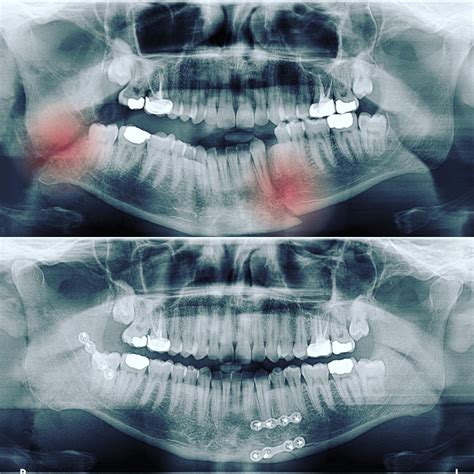

Before any incision is made, the surgical team must obtain a high-definition map of the damage. Modern medical imaging has revolutionized face trauma surgery, allowing surgeons to visualize fractures in three dimensions. Using CT scans and Cone Beam Computed Tomography (CBCT), doctors can identify displaced bone fragments that are not visible to the naked eye. This data is critical for planning the placement of titanium plates, screws, and mesh grafts.

• Functional stability: Ensuring the jaw aligns correctly to facilitate proper dental occlusion.

Surgeons typically employ "open reduction and internal fixation" (ORIF) as a standard for treating complex fractures. This involves repositioning the bone segments and securing them with specialized hardware. Below is a summary of the common materials and approaches used in the operating room.

Titanium Micro-plates Provides structural support to bone fractures while healing.